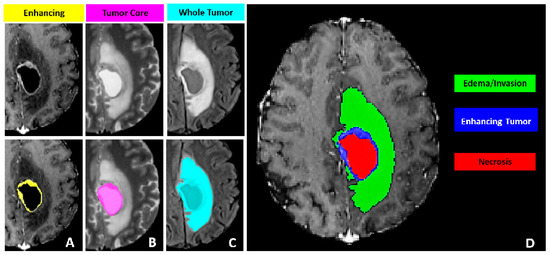

The tumor sub-regions annotated are based on observable features recognizable by trained radiologists (referred to as VASARI features) and include the following. The Gd-enhancing tumor (ET) labeled as 4, which represents the enhancing part of the tumor visible on T1Gd MRI scans, including areas of strong and faint enhancement. The peritumoral edematous/invaded tissue (ED) labeled as 2, which is characterized by an abnormal hyperintense signal on T2-FLAIR volumes, encompassing the infiltrative non-enhancing tumor and vasogenic edema in the peritumoral region. The necrotic tumor core (NCR) labeled as 1, which appears hypointense on T1Gd MRI and represents the non-viable, necrotic center of the tumor. This is illustrated in Figure 5.

Figure 5. Glioma sub-regions considered in the MICCAI BRATS 2021 challenge. (A) displays the enhancing (yellow) and tumor core (pink) areas; (B) shows the whole tumor (light blue) area; (C) presents the edema/invasion (green) and enhancing tumor (blue) areas; (D) depicts the necrosis (red), enhancing tumor (blue), and edema/invasion (green) areas, comprehensively representing the different sub - regions of the tumor.